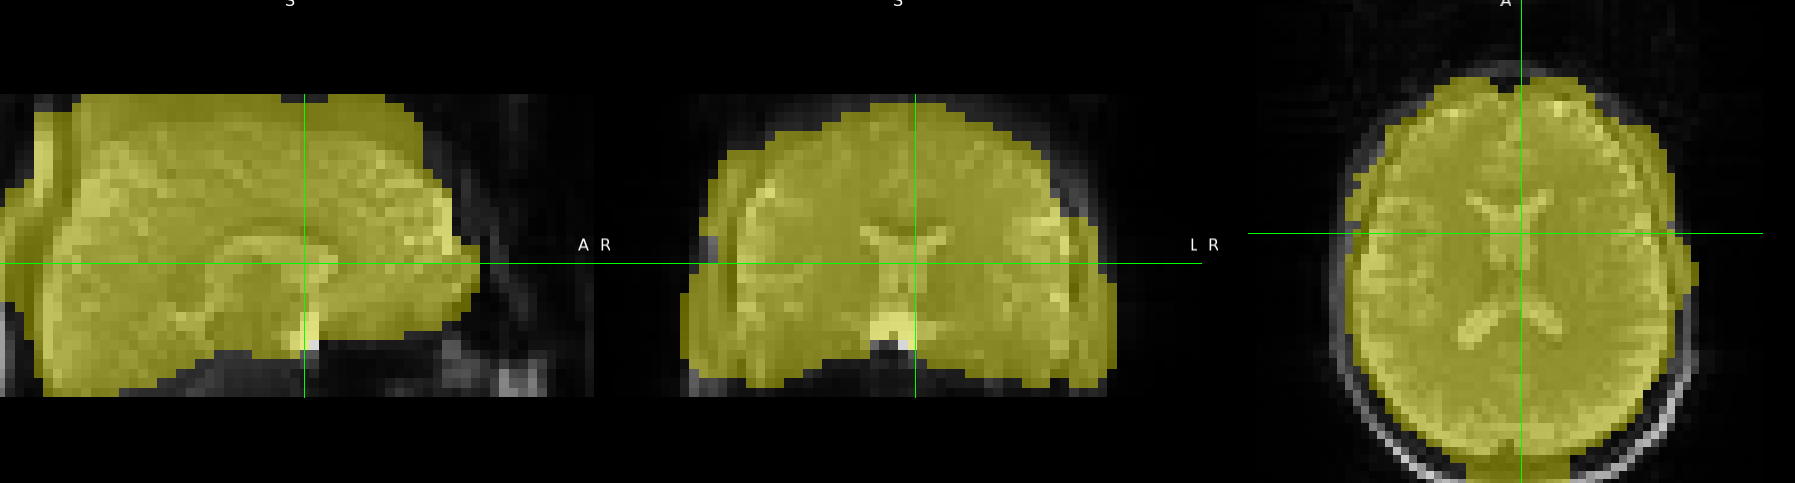

I tried running ASLPrep on several subjects, but the brain masks it produced were all very strange. In contrast, when I applied BET directly, the results were correct.